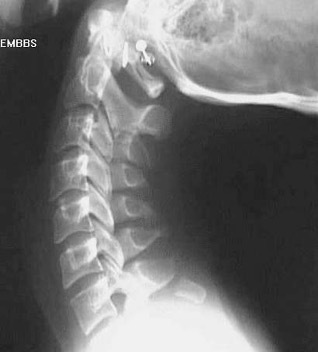

Q

What fractures are present here?

Lateral x-ray shows spinous process fractures from C3 to C5. Bilateral fracture of C6 laminae.

The patient is wearing a cervical collar.